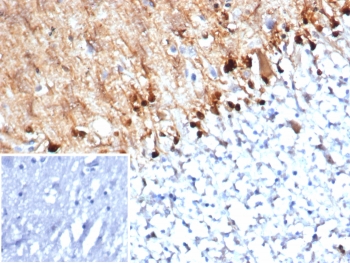

Immunohistochemistry analysis of S100B / Brain Injury Biomarker antibody (clone S100B/4152) in human brain tissue. FFPE human brain demonstrates strong cytoplasmic and nuclear HRP-DAB brown staining in astrocyte-like cells distributed throughout the parenchyma, consistent with S100B expression. Staining highlights cells with branching processes characteristic of astroglial morphology, while neuronal cell bodies show comparatively weaker signal. Nuclei are counterstained blue. The inset image represents a secondary antibody negative control in which PBS was used in place of the primary antibody and shows absence of specific staining. Heat induced epitope retrieval was performed by boiling tissue sections in 10 mM Tris with 1 mM EDTA, pH 9.0, for 20 minutes followed by cooling prior to immunostaining.